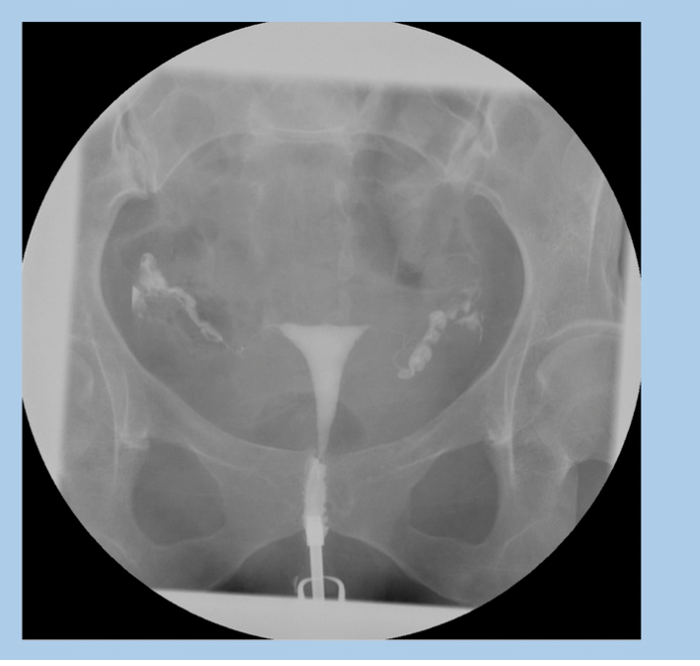

Hysterosalpingogram

Commonly used for investigation of infertility/miscarriage

Assess normal shape of uterine cavity, patency of fallopian ducts, free spill of contrast into interperitoneal space

A hysterosalpingogram (HSG) isan X-ray dye test used to diagnose problems related to fertility.

Hysterosalpinogram

Used to assess patency of fallopian tubes